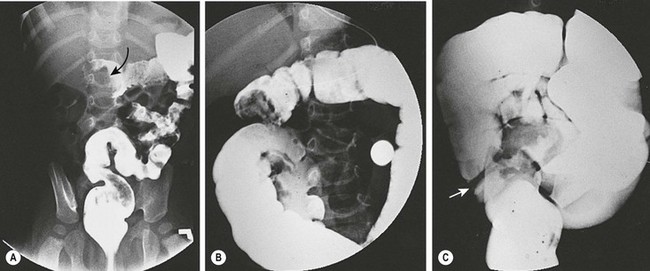

FIGURE 38-7 Fluoroscopic examination using isotonic contrast for hydrostatic reduction of intussusception. (A) Intussusception (arrow) seen in midtransverse colon. (B) Reduction has occurred to the hepatic flexure. (C) Complete reduction with reflux of contrast medium into the terminal ileum. Note the edematous ileocecal valve (arrow).